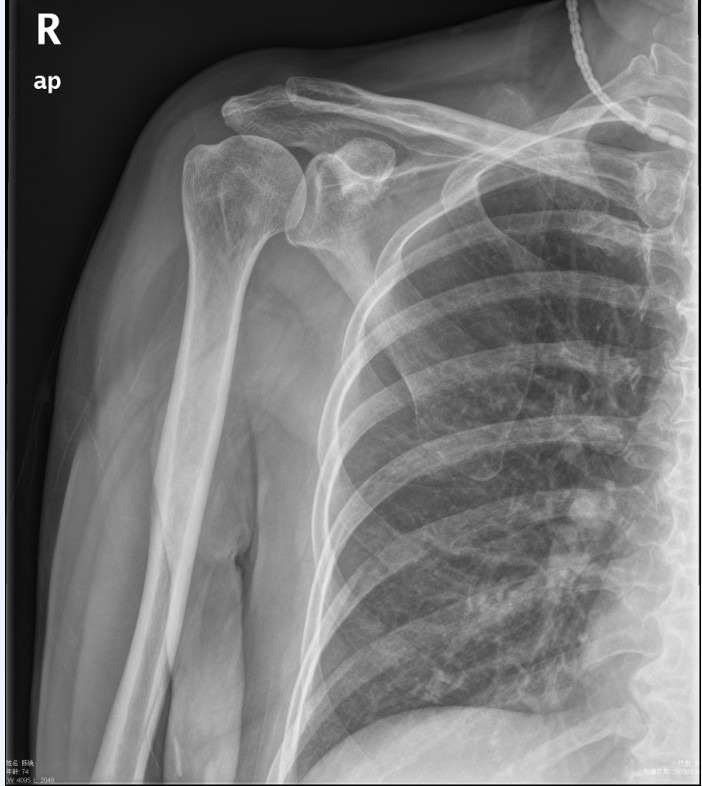

标题: CT19811:女,76岁,右上臂肿物1个月 [打印本页]

标题: CT19811:女,76岁,右上臂肿物1个月

右肱骨上段软组织内见梭形低密度影,边界清楚,最长径约54mm.

病理结果:脂肪瘤。术中见肱骨骨膜受侵,有出血,量不详。

当时诊断意见:右肩三角肌内蔓状血管瘤(先天性动静脉瘘)。